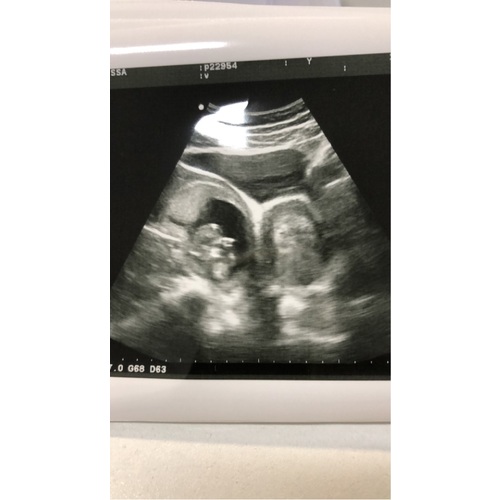

Oude topic, maar vond hem terug toen ik gericht ging zoeken. Ik ben er sinds oktober achter gekomen dat ik een dubbele baarmoeder heb met 1 hals en 2 hoornen. Wel heb ik gewoon 2 nieren en ziet alles er verder goed uit. Omdat mijn cyclus al bijna 2 jaar erg onregelmatig was na het stoppen met de pil, kwamen we bij de gynaecoloog terecht. Pas bij de derde controle was er een gynaecoloog die erachter kwam. Toen even in twijfel gezeten of we het zwanger worden wel aandurfden omdat je toch vaak hoort over vroeggeboortes en miskramen… toch de stap genomen en nu na 1x een hormoontabletten stripje al ongeveer 6 weken zwanger. Ik kan het nog niet helemaal bevatten. Buitenom dat ik vaak moet plassen en soms wat opgeblazen ben, nog geen symptomen verder. We hebben afgelopen week al een eerste echo gehad en daarop zag alles er goed uit. Het is goed ingenesteld en er was zelfs al een hartslagje te zien. Nu blijf ik wel in mijn achterhoofd houden dat het zomaar mis zou kunnen gaan. Maar ben natuurlijk ook erg benieuwd naar verhalen van dames die in het zelfde schuitje zitten of hebben gezeten als ik ☺️